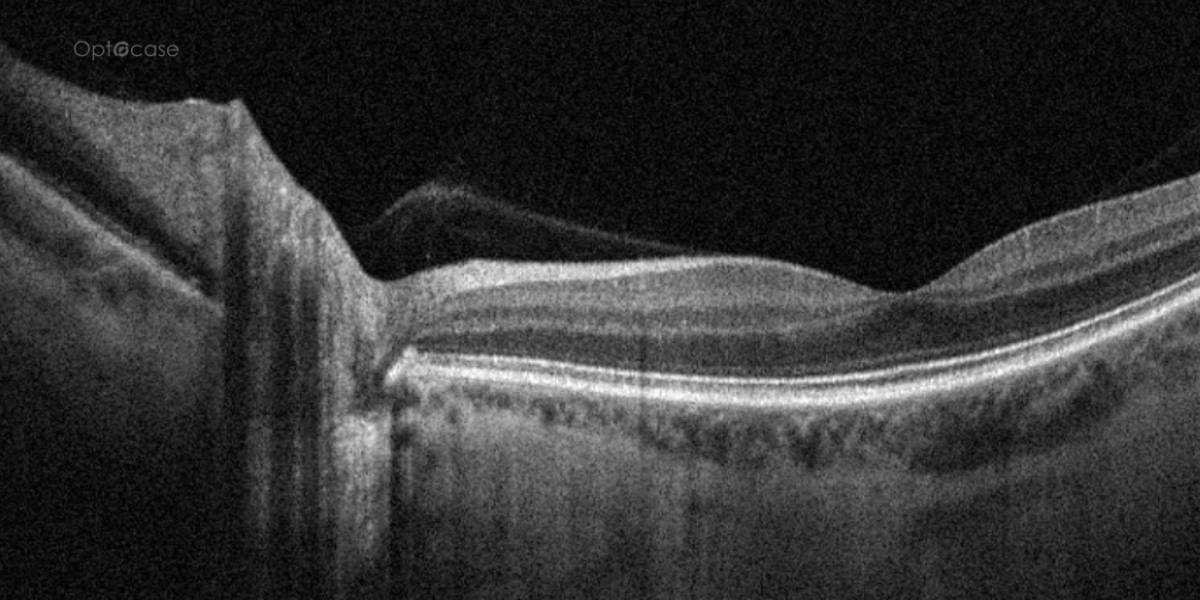

Here there is loss of the regular macular depression. There is a bright line present on the surface of the retina. In addition, there is separation of the retinal layers in the inner retina.

The patient was diagnosed with a schisis secondary to an epiretinal membrane. This complication is seen in over 50% of ERMs (video).

- Where the vitreous is adherent to the retina